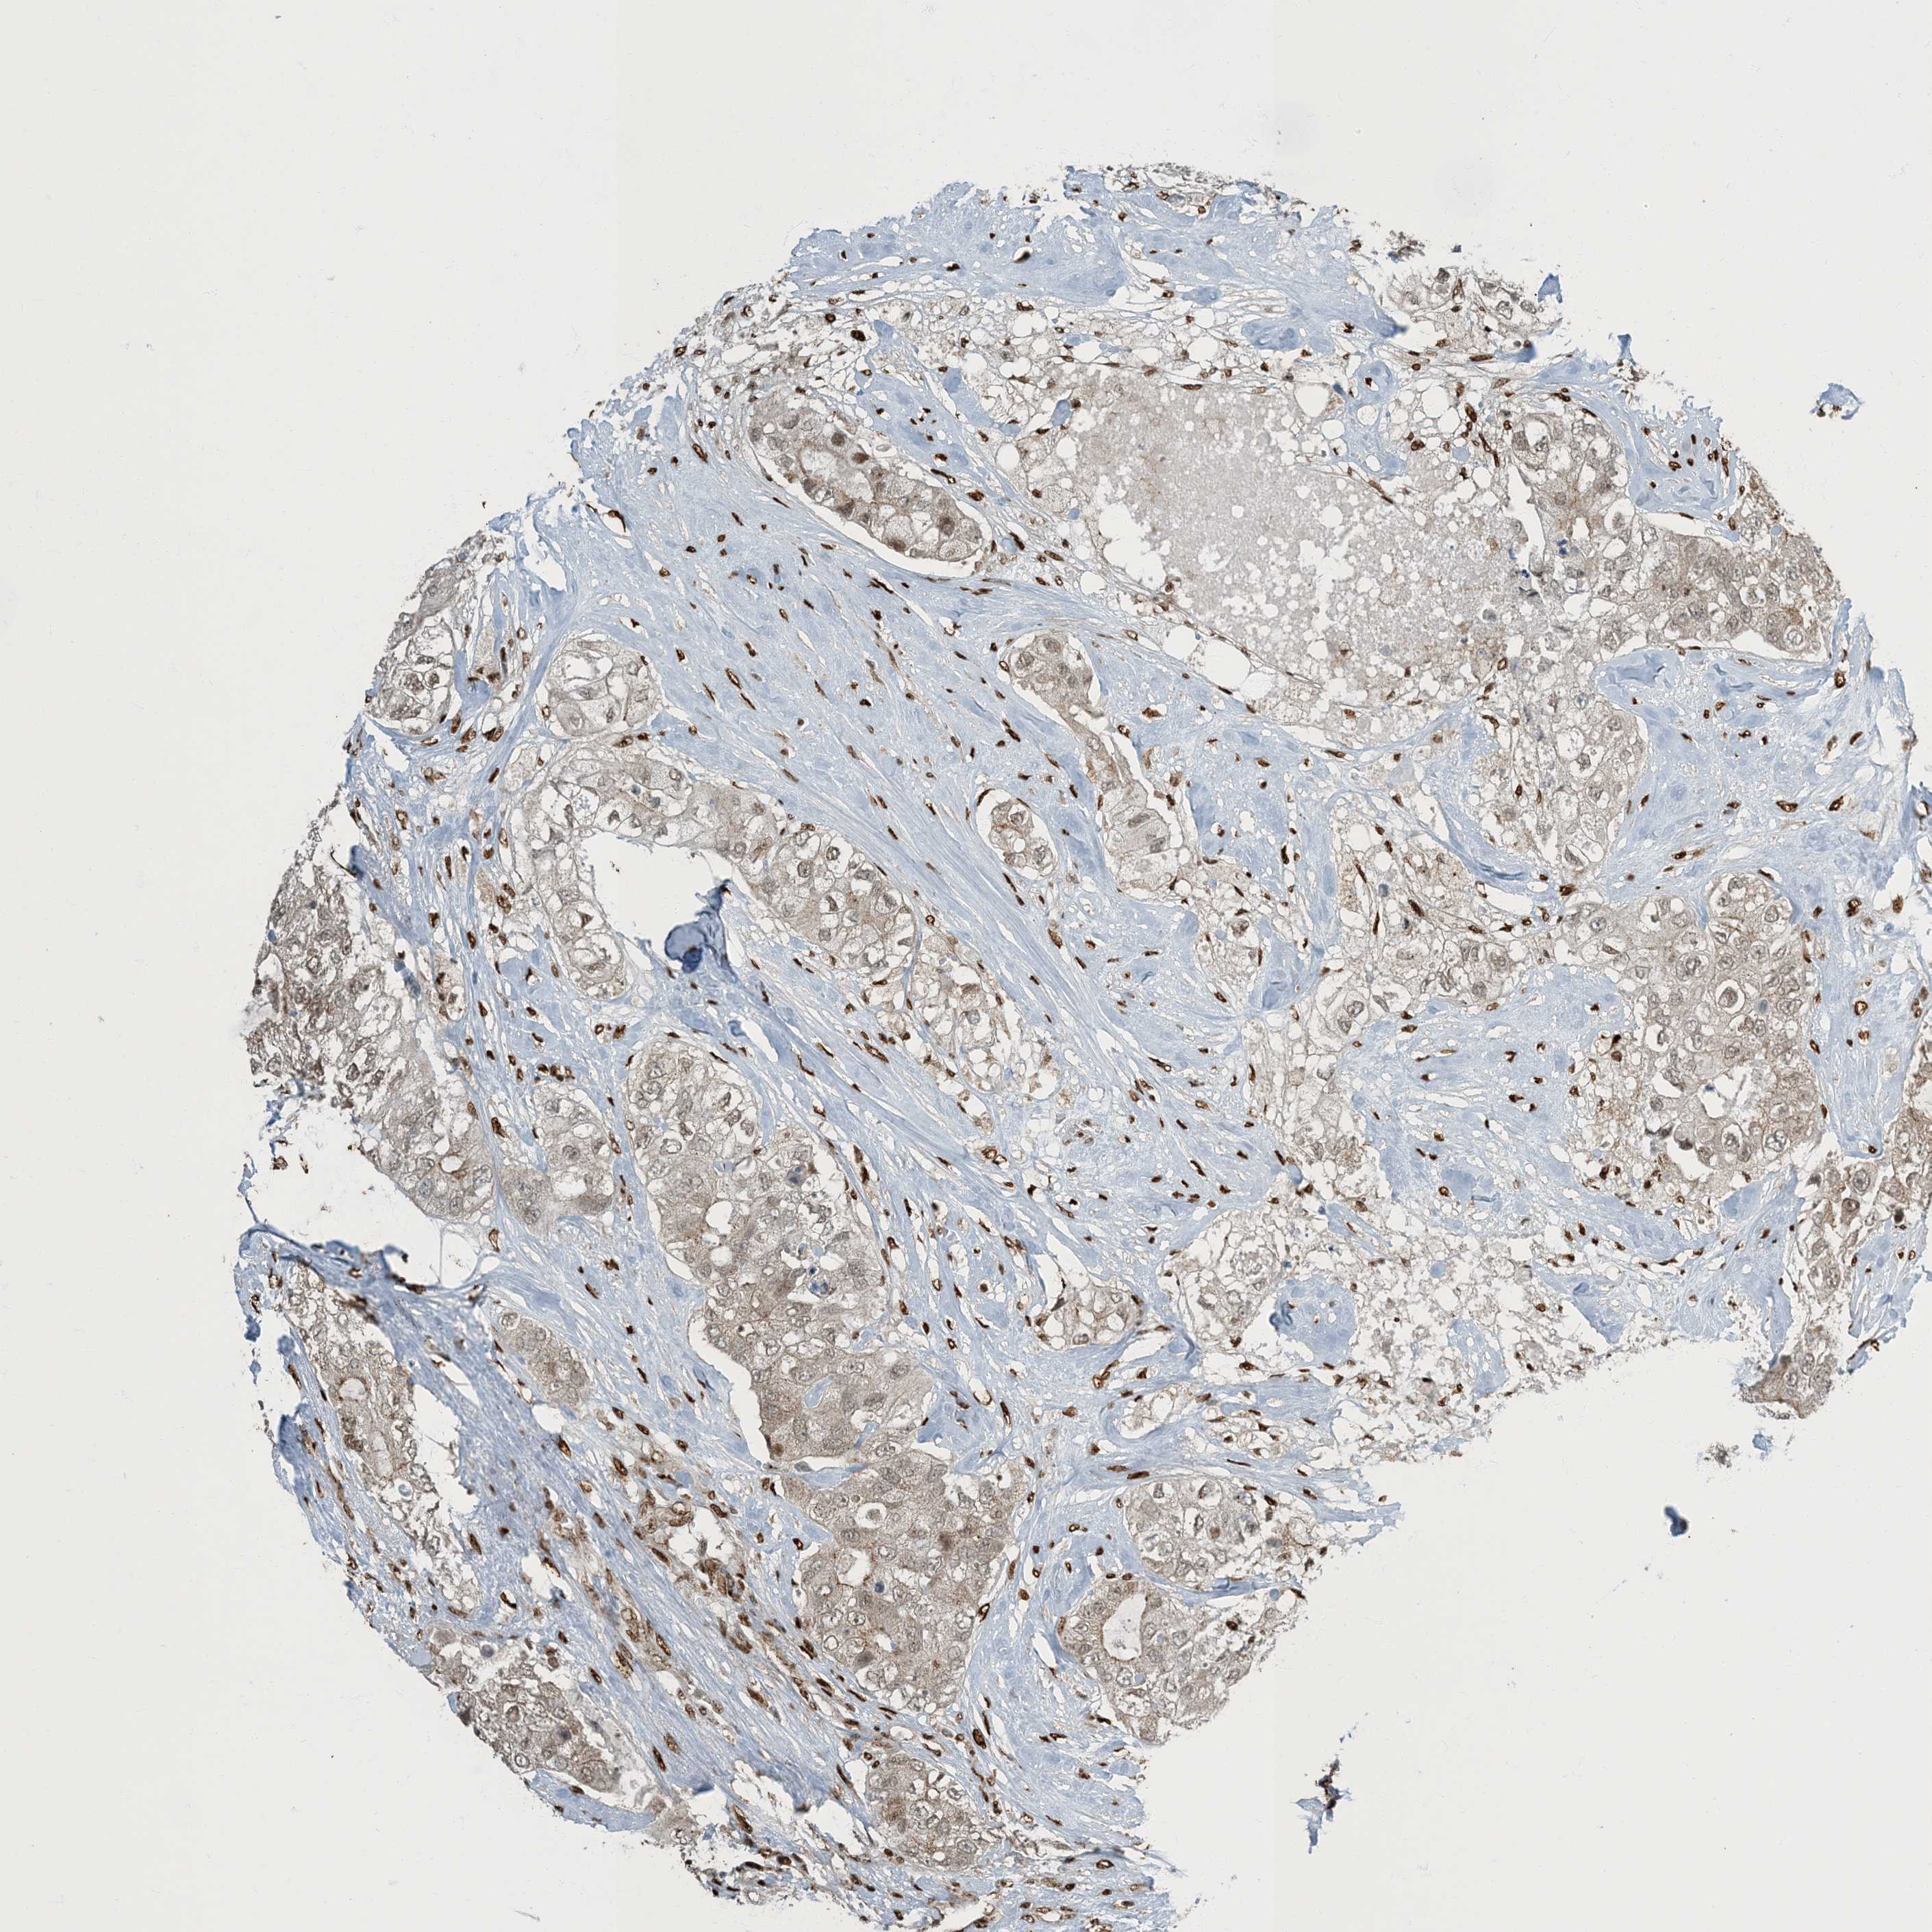

CANCER BREAST CANCER Show tissue menu

BRCA TCGA BRCA VALIDATION PROTEIN EXPRESSION